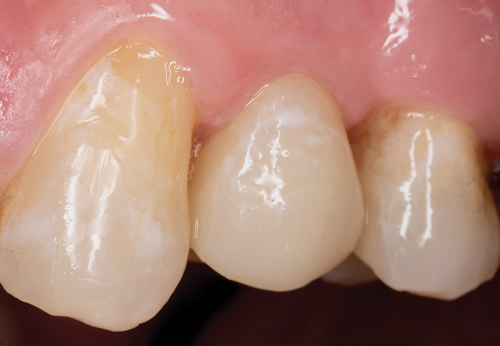

The clear silicone matrix was placed over the posterior segment of the maxillary arch, and an opacious A2-shaded injectable flowable universal resin composite was injected through a small opening above the preparation and fiber post (Figure 20 and Figure 21). The resin composite was cured through the clear resin matrix on the incisal, facial, and lingual aspects for 40 seconds each. Upon removal of the matrix, the excess polymerized composite resin was removed with a #12 scalpel blade, and the incisal sprue was removed using a tapered diamond finishing bur. A round, tapered diamond bur was used to establish the gingival margin (Figure 22) and a needle-shaped finishing bur was used to complete the finishing of the preparation.

Fig 22. The preparation was completed using a tapered diamond bur.